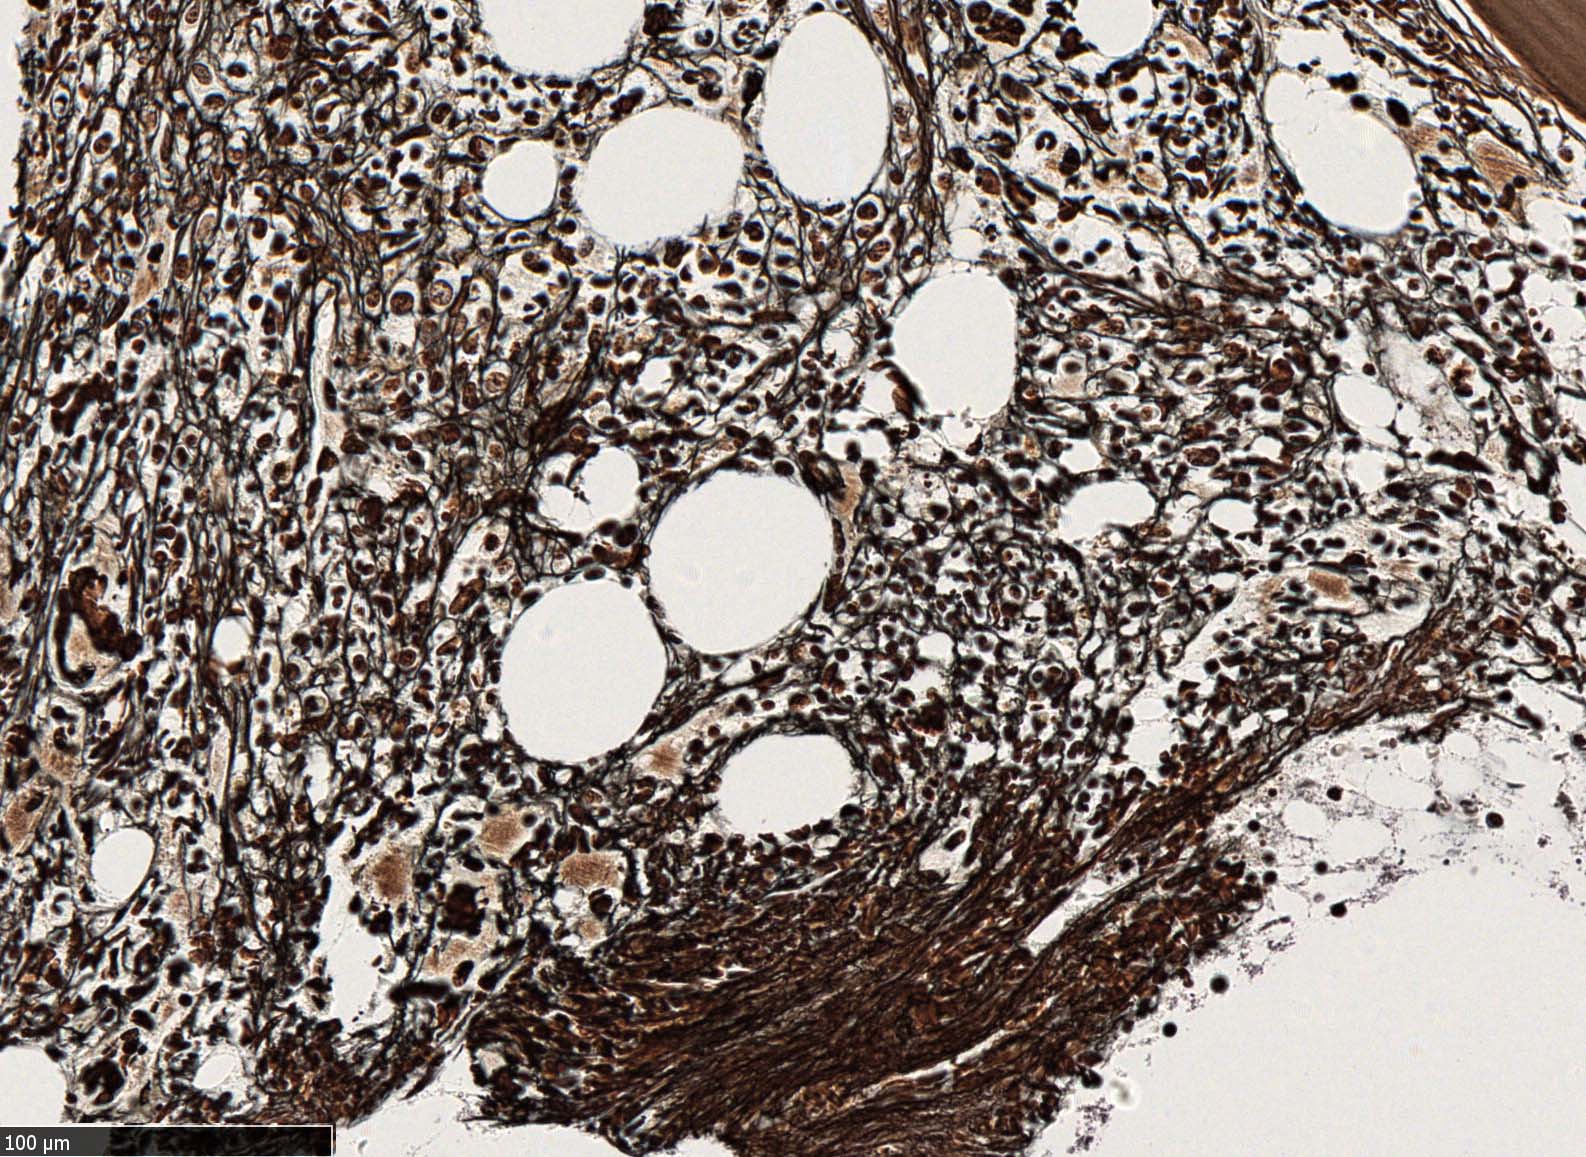

塗銀染色